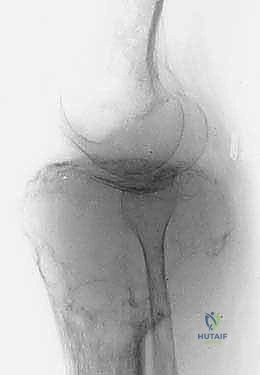

لفهم مدى تعقيد وعبقرية جراحة استئصال الظنبوب القريب، من الضروري الإبحار في أعماق التشريح الأساسي لهذه المنطقة الحيوية. لا يقتصر الأمر على مجرد عظام، بل هو نظام هندسي وبيولوجي متكامل ومعقد. يتكون مفصل الركبة من التقاء عظم الفخذ (Femur) من الأعلى، وعظم الساق أو الظنبوب (Tibia) من الأسفل، وعظم الشظية (Fibula) الجانبي، بالإضافة إلى الرضفة أو صابونة الركبة (Patella) في الأمام. الجزء القريب من الظنبوب هو الجزء العلوي العريض من عظم الساق، والذي يشكل القاعدة الأساسية التي يستند عليها مفصل الركبة ويتحمل وزن الجسم بأكمله.